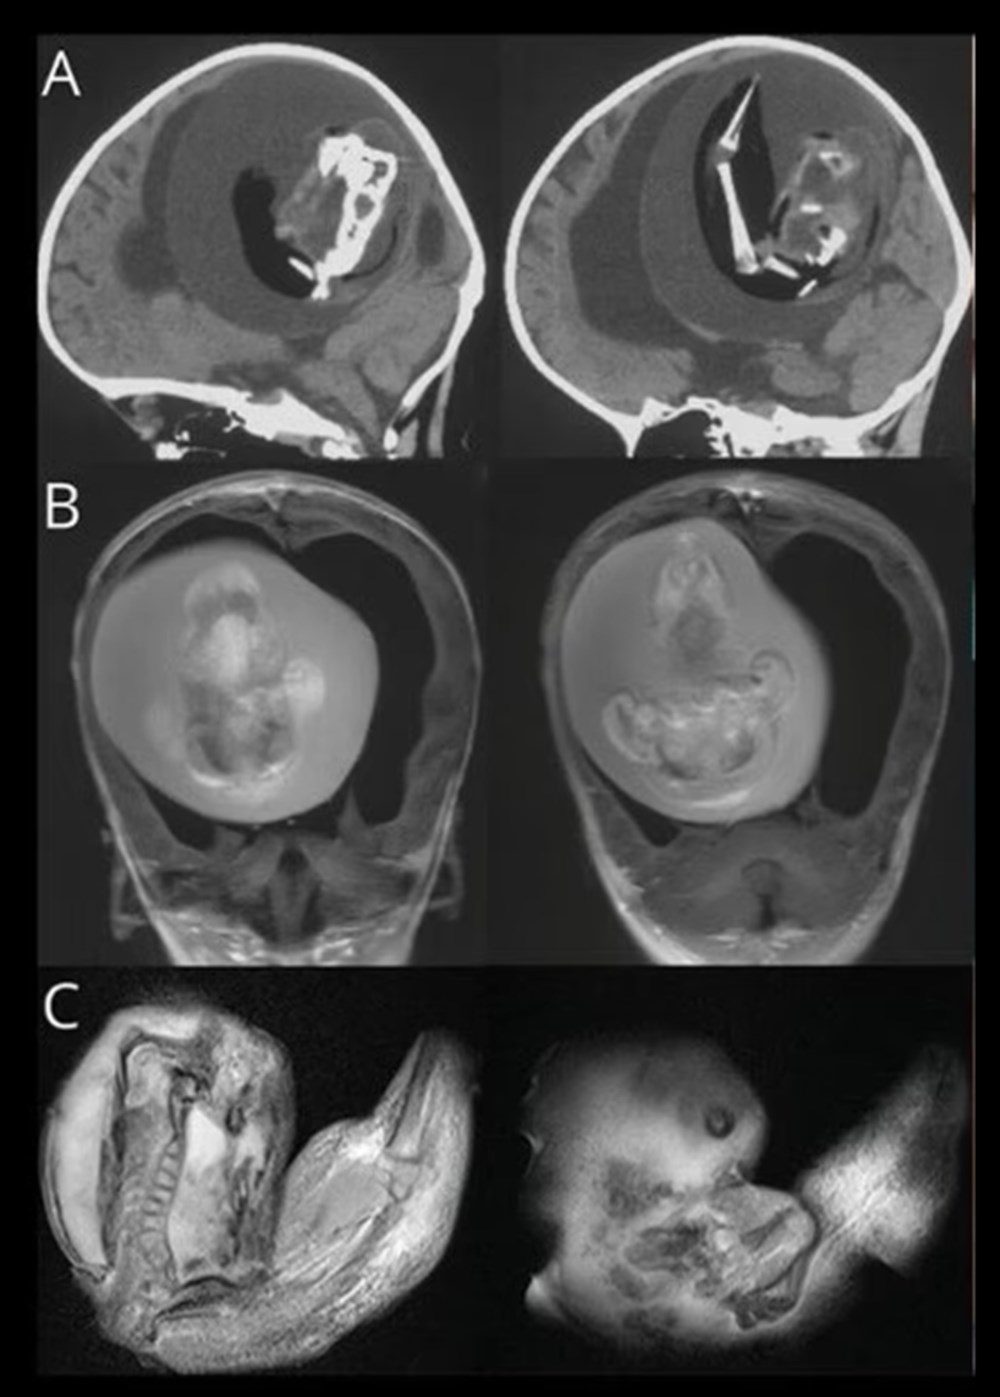

Yeni bir araştırmaya göre, Çin’de doktorlar bir yaşındaki bir çocuğun beyninde ‘doğmamış ikizinin fetüsünü’ buldu. Neurology dergisinde yayınlanan çalışmada, çocuğun motor fonksiyonlarında sorunlar yaşaması ve kafasının büyümesi üzerine ebeveynleri tarafından hastaneye getirildiği ortaya çıktı. Şangay’daki doktorlar, doğmamış ikizin fetüsünün çocuğun beyninde geliştiğini tespit etti. Çalışmanın yazarları, “Motor becerilerinde gecikmesi ve genişlemiş baş çevresi olan 1 yaşındaki bir kız çocuğunda malforme olmuş monokoryonik diamniyotik ikiz olan intraventriküler fetüs içinde fetüs (fetus-in-fetu) tespit edildi.” denildi.

Parazit ikiz olarak da adlandırılan fetüs içinde fetüs, ikizlerin rahimde yapışık olması, ancak yalnızca birinin gelişmeye devam etmesi durumunda ortaya çıkıyor. Çalışmada, genom dizilimi sonrasında fetüsün çocuğun ikizi olduğunun tespit edildiği de belirtildi.

Bununla birlikte fetüs içinde fetüs vakaları ikiz gebeliğin çok erken aşamalarında, döllenmiş bir yumurta tarafından oluşturulan ve blastosist olarak adlandırılan bölünen hücre kümesinin düzgün bir şekilde ayrılamamasıyla meydana geliyor. Ardından embriyolardan biri diğeri tarafından çevreleniyor.

Diğer ikizin çoğalan hücreleri tarafından sarılan öteki fetüs gelişemiyor, ancak kan desteği aldığı için “canlı” kalıyor.  Çalışmada, “Yapışık parçalar ana fetüsün ön beynine dönüşüyor ve nöral plak katlanması sırasında diğer embriyoyu sarıyor.” ifadeleri kullanıldı.